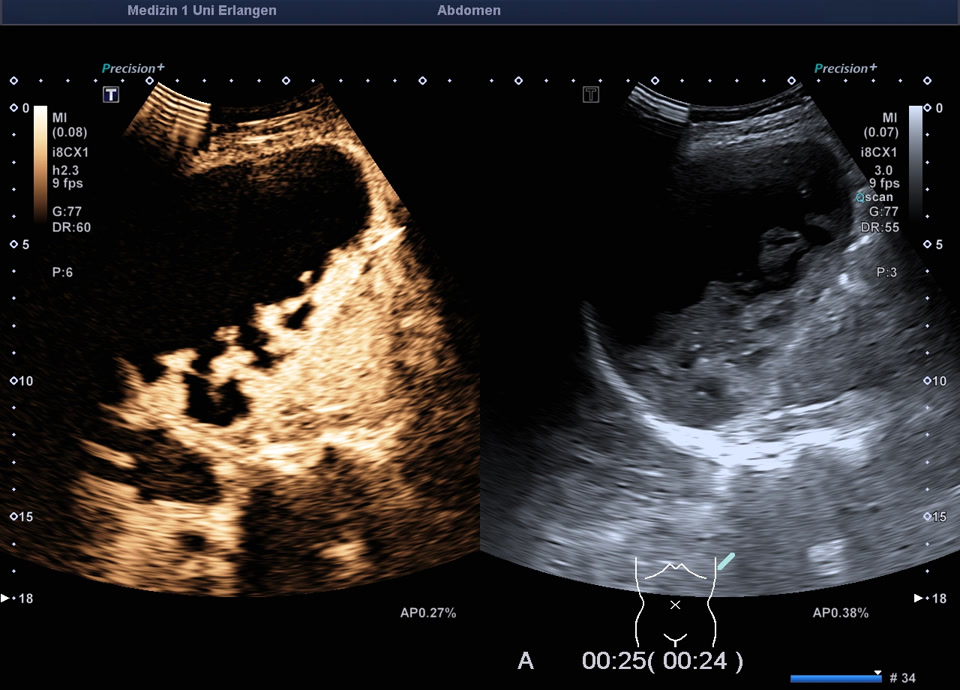

Kasuistik: 57-jährige Patientin mit einer Granulomatose mit Polyangiitis mit unklarer Leberwerterhöhung (ohne abdominelle Symptomatik). Im Ultraschall zeigt sich ein überraschender Milzbefund: Die Milz stellt sich großteils liquide dar, mit nur einem geringen Anteil soliden Gewebes, die Milzkapsel ist intakt. Die Kontrastmittelsonographie zeigt wenig erhaltenes und kontrastiertes Milzparenchym, ohne KM-Austritt in die flüssigen Anteile. Ein Trauma ist auf explizite Nachfrage nicht erinnerlich. Der Befund entspricht dem seltenen Fall einer asymptomatischen subtotalen Milznekrose, am ehesten im Rahmen einer nekrotisierenden Vaskulitis.